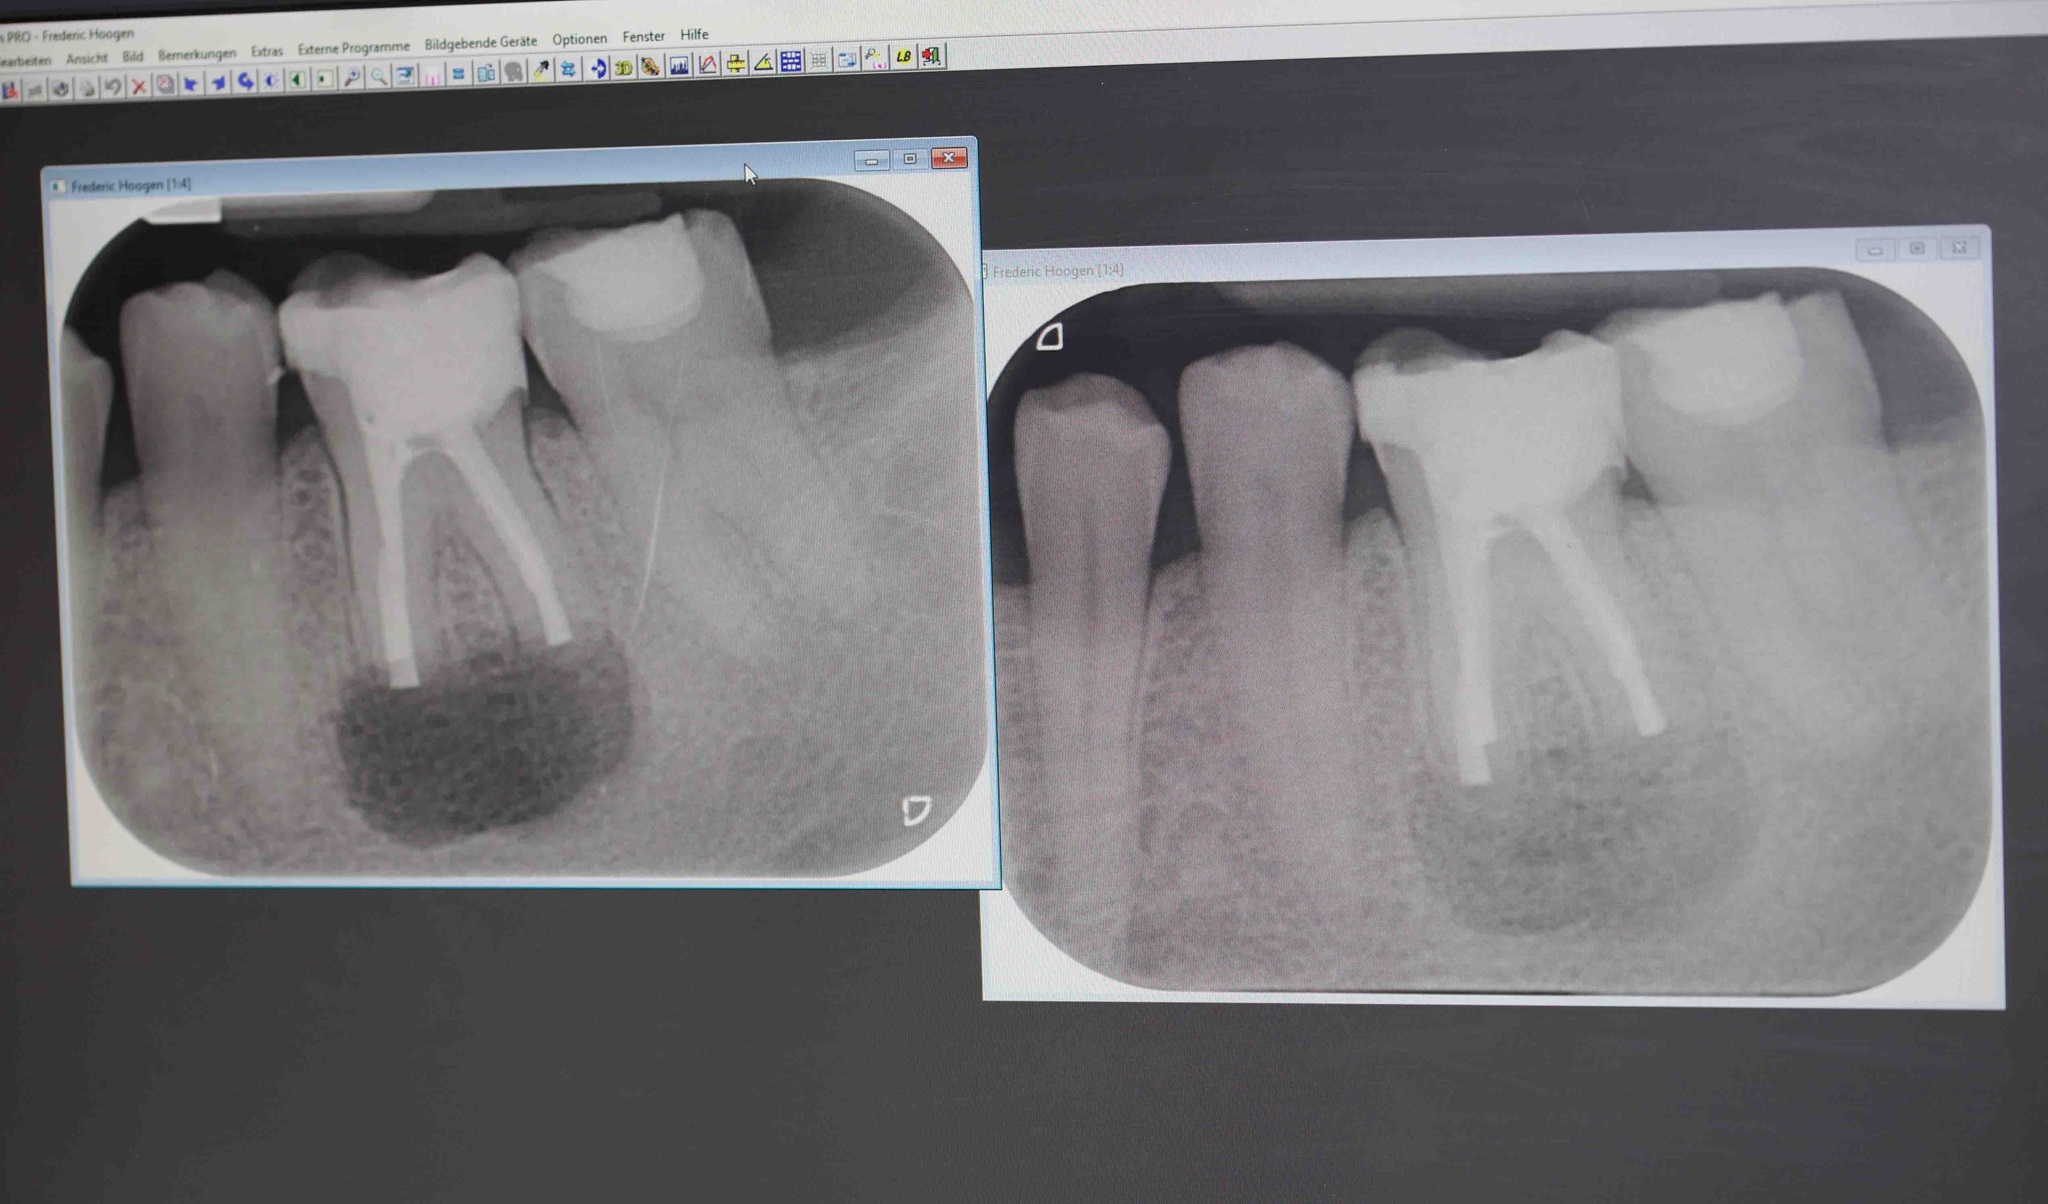

Eine Entzündung des Zahnmarks (Zahnnerv) kann sich auch auf die Austrittsstellen der Nervkanäle ausdehnen und so die Wurzelspitze und den um­liegenden Kieferknochen erfassen. Es entstehen chronisch entzündliche Prozesse, so genannte Herde, die unter Umständen durch eine alleinige Wurzelkanalbehandlung nicht zu beseitigen sind. Manchmal bildet sich auch erst nach erfolgter Wurzelkanalbehandlung an der Wurzelspitze ein Herd aus. Im Kiefer liegende Entzündungsherde sollten immer entfernt werden, auch wenn sie aktuell "stumm" sind, also keine Schmerzen verursachen. Bakterien und deren giftige Stoffwechselprodukte können sich über die Blutbahn im gesamten Organismus verbreiten und so das Immunsystem schwächen bzw. schwere Erkrankungen begünstigen. Zudem ist jederzeit ein akutes Aufflammen der Entzündung möglich. Damit verbunden sind Schwellungen, Eiteransammlungen und Abszesse, die schmerzhaft und sogar gefährlich sind. Nicht selten treten diese Beschwerden unpassend z.B. im Urlaub oder an Wochenenden auf. Um den Zahn zu erhalten ist in vielen Fällen eine so genannte Wurzel­spitzenresektion (operative Entfernung der Wurzel­spitze) möglich. Hierbei wird die Entfernung der Wurzelspitze des betreffenden Zahnes und des umliegenden entzündeten Gewebes durchgeführt. Außerdem werden die Wurzel­kanäle gereinigt, desinfiziert und mit einer Füllung abgedichtet. Wann eine chirurgische Zahnerhaltung im Einzelfall noch sinnvoll ist und welche Methode dabei am meisten Erfolg verspricht, muss immer individuell beurteilt und mit dem Patienten besprochen werden. Mögliche Risiken für wichtige anatomische Strukturen wie z.B. Nerven müssen abgewogen werden.